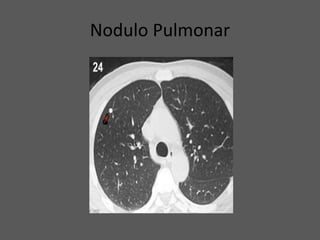

NODULO PULMONAR